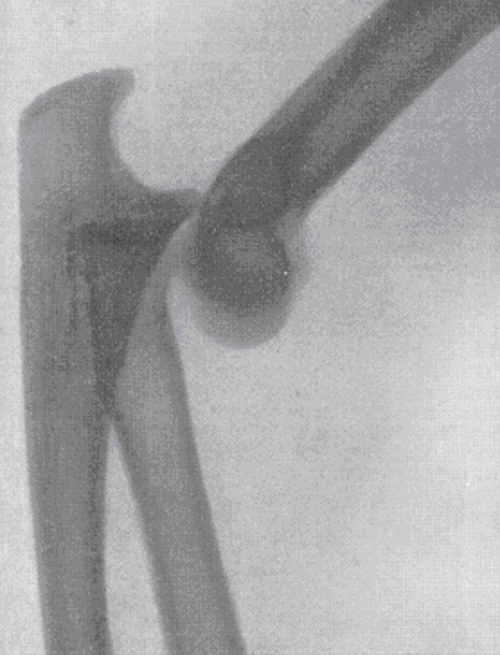

Запитання 19

РОЗПІЗНАЙТЕ НА РЕНТГЕНОГРАМІ СУГЛОБ, ЩО СКЛАДАЄТЬСЯ З ТРЬОХ СУГЛОБІВ, ЯКІ МАЮТЬ СПІЛЬНУ КАПСУЛУ.

варіанти відповідей